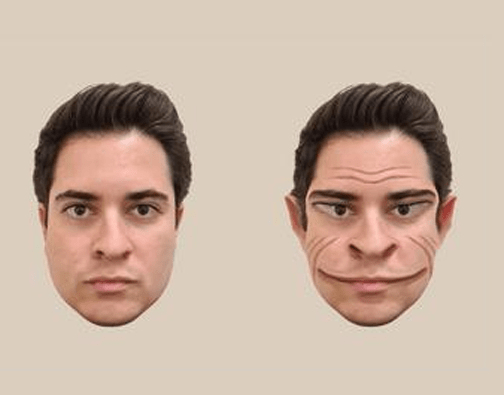

58 yaşında ABD’li bir erkek, dünyayı çoğumuzdan farklı bir şekilde görüyor. Bu fark insan yüzünü algılayışından kaynaklanıyor çünkü o, yüzleri insan yüzü olarak değil, bir yaratık olarak görüyor. Buna prosopometamorfopsi ya da kısaca PMO deniyor. Bu adam Dartmouth College’deki deneylere katılmadan önceki iki buçuk yılını çevresindeki yüzlerde delikler oluştuğunu, yanaklarda, alınlarda ve çenelerde buruşukluklar belirdiğini, gözlerin ve ağızların gerildiğini kulakların elf kulağına dönüştüğünü görmek zorunda kaldı. İlk başta rahatsız edici bir durum olsa da adam, zihninin dayattığı bu maskelere zaman içinde alıştı. Sonuçta dehşet hissi yaratsa da bunlar gerçek iblisler değildi ya.

Ama dikkat edilmesi gereken bir nokta var: Bu adam bu duruma nasıl geldi? Hayatının tamamını böyle geçirmemişti. Belki bipolar bozukluktan ya da travma sonrası stres bozukluğundan kaynaklanıyordu bu durum. Ya da 40’lı yaşlarının başında geçirdiği ciddi kafa travmasının bir sonucuydu. Psikologlar konunun üzerine eğildiklerinde deneğin PMO’yu hiç de tipik olmayan bir şekilde deneyimlediğini fark ettiler. Normalde diğer PMO’lu hastalar hem insan yüzünü hem de fotoğraflarını çarpıtılmış halleriyle görürken denek sadece gerçek hayattaki yüzleri çarpıtılmış olarak görüyordu. Fotoğraflarla ilgili herhangi bir sorunu yoktu.

Böylelikle psikologlar bir odadaki gönüllülerin fotoğraflarını deneğe göstererek hastanın bakışındaki farklılığını gözlemleyebildi. İşte Lancet’te yayınlanan çalışmada ortaya çıkan sonuç şöyle:

Hastanın algıladığı şekliyle erkek yüzündeki çarpıklıkların algılanış şekli bilgisayarda böyle oluşturulmuş. Fotoğraf: The Lancet

Bu arada çalışmaya konu olan kişinin hastalığının hipokampüsünün sol üst kısmında görülen bir cm’lik küçük bir lezyonun sorumlu olabileceği düşünülüyor.